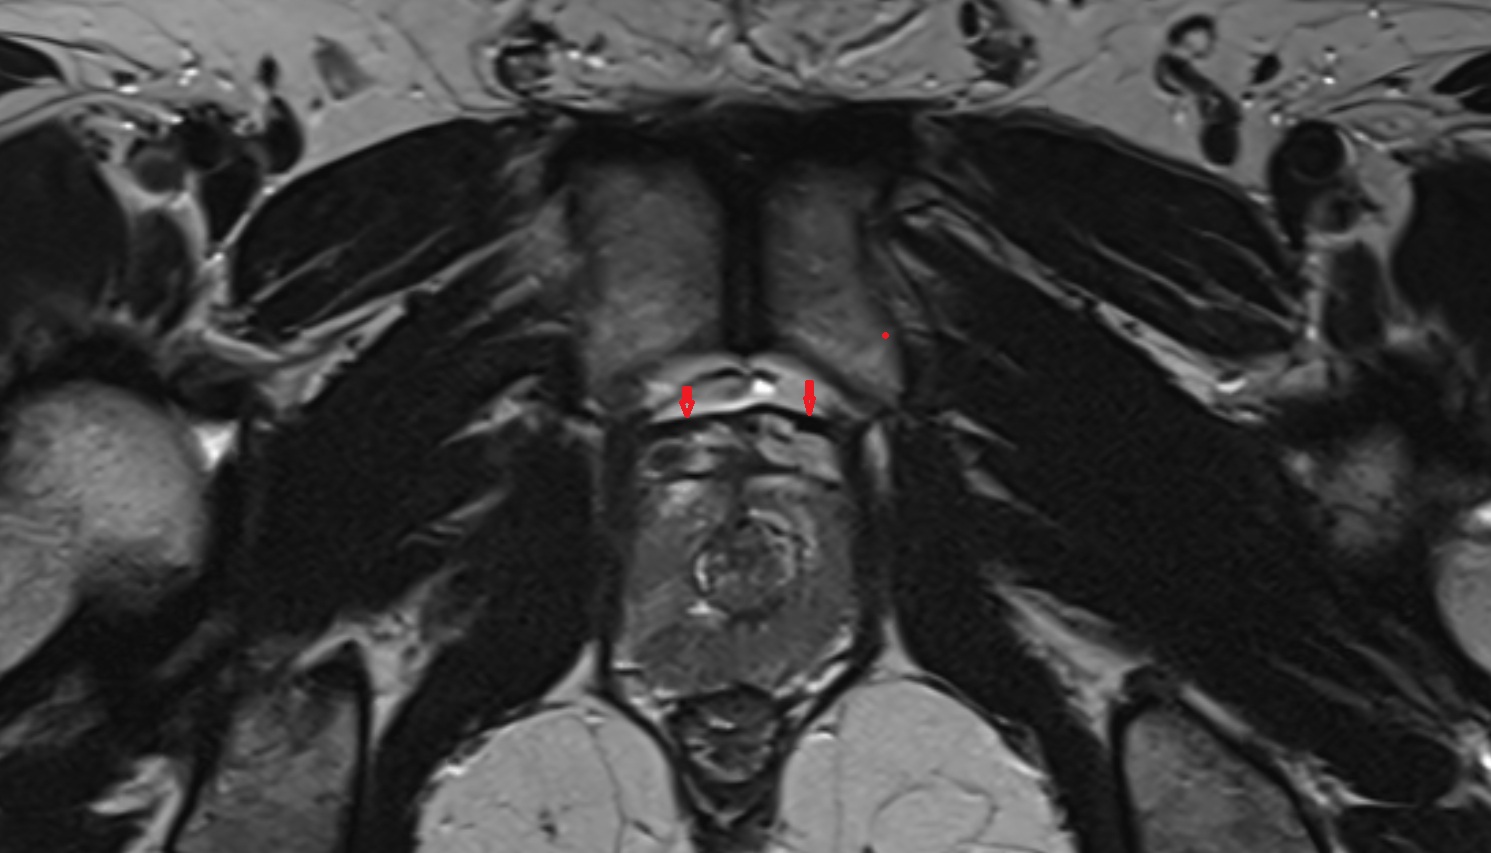

- Peripheral zone of prostate

- Anterior Fibromuscular Stroma of prostate

- Central zone of prostate

- Transitional zone of prostate